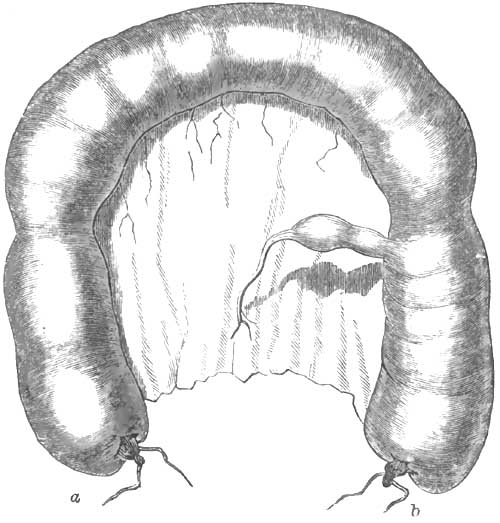

| 24. | POSTERIOR VIEW OF A STRANGULATED INTESTINE AND STRICTURE |

| 25. | APPEARANCE OF THE NATURAL RELATIONS OF THE DIVERTICULUM TO THE INTESTINE |